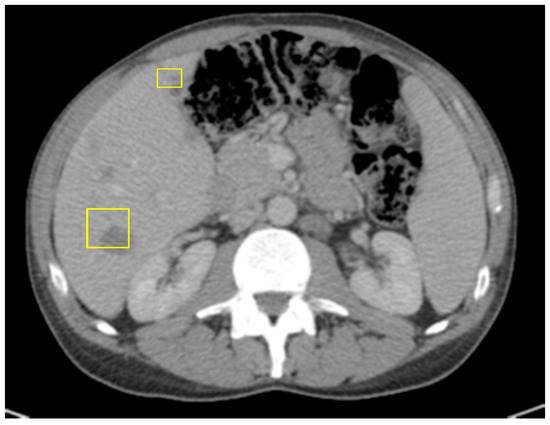

The patient was initially given neoadjuvant systemic therapy with FOLFOX (folinic acid, 5-fluorouracil, oxaliplatin). After two months of treatment, repeat CT imaging demonstrated a reduction in the size of the cecal mass and mesenteric lymph nodes, and his serum carcinoembryonic antigen (CEA) level had decreased to 2.3, indicating a favorable initial response. A laparoscopic-assisted right hemicolectomy with anastomosis and omentectomy was performed. The surgical pathology demonstrated a T4 tumor with invasion into the abdominal wall, though the resection margins were negative. However, a postoperative CT scan of the abdomen and pelvis performed three days later revealed new multiple hepatic metastases (Figure 3).

Figure 3. CT of abdomen/pelvis with IV contrast 3 days post right-sided hemicolectomy of primary colon cancer with curative intent.